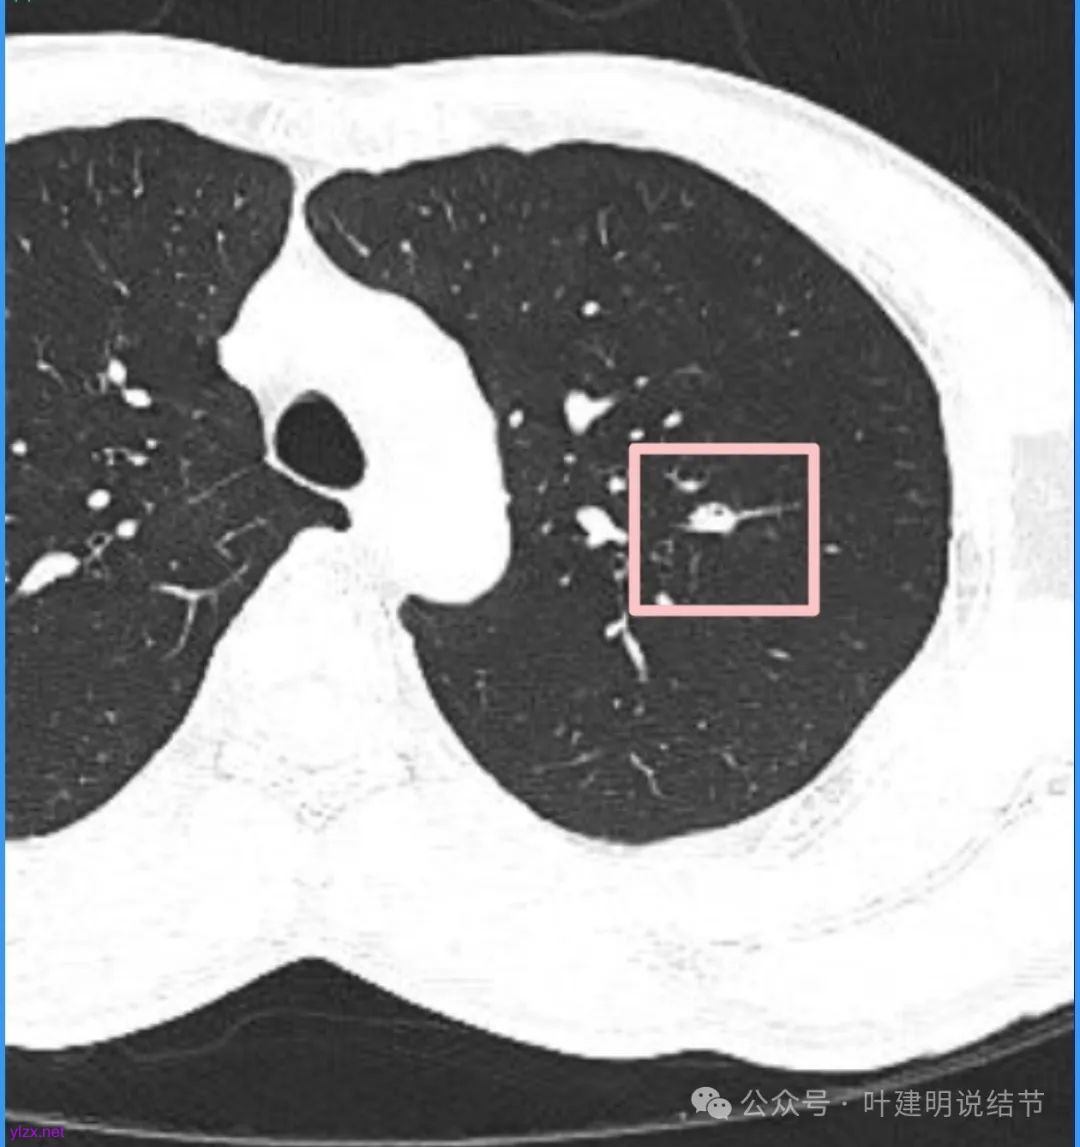

我们先来看2025年3月时的影像:

病灶密度不均,混合密度的样子,相应的细支气管有扭曲略显扩张。

边缘较为毛糙不平,灶内密度杂乱,细支气管穿行,整体轮廓较清。

邻近血管受结节影响,略向病灶侧弯,病灶处是扩张的细支气管还是灶内的空泡征?

有血管征,整体轮廓与边界较清,灶内有蜂窝状。

血管穿过病灶,灶内多个小空泡,整体轮廓较清。

蓝色部分似乎是血管,但似乎又是增厚的支气管壁,局部细支气管扩张。

特别上上图边缘些的层面,蓝色箭头所指的实性明显又像位于扩张细支气管内或与支气管壁一块的样子。